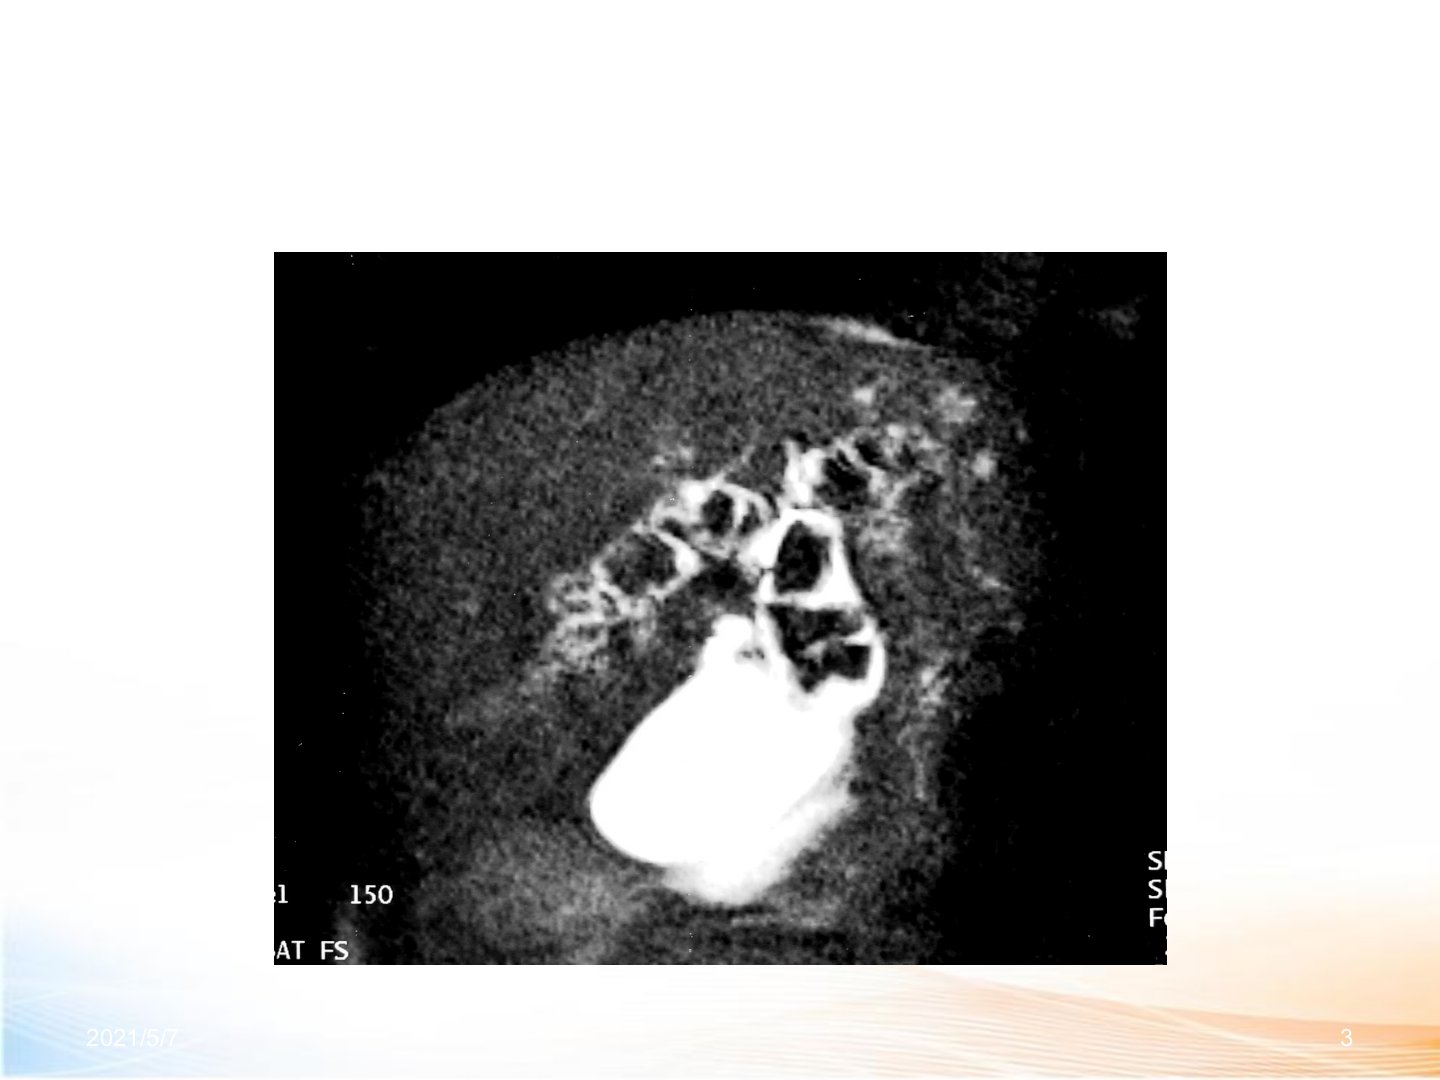

肝胆管结石的诊治进展摘要肝胆管结石指左右肝管汇合部以上胆管结石多为原发性肝内胆管结石。其发病机理涉及胆道感染、胆汁淤积、胆道寄生虫及代谢因素等可形成恶性循环导致病情复杂、并发症多、复发率高以胆色素结石为主病变多见于左肝外叶及右肝后叶。临床表现上静止期多无症状或有肝区钝痛、慢性胃病症状;急性发作期则有不同类型急性化脓性胆管炎。诊断方面结合临床表现并借助B超、CT、MRCP、ERCP、PTC及数字医学技术等辅助检查。治疗原则为去除病因、解除梗阻、通畅引流。治疗方法多样手术治疗包括肝部分切除术、胆总管切开探查取石引流术等;术后残石处理及非手术治疗有经T管窦道、皮下通道纤维胆道镜取石等;十二指肠镜应用、介入治疗等也有进展;微创技术联合应用、肝移植术也为治疗提供新方向。